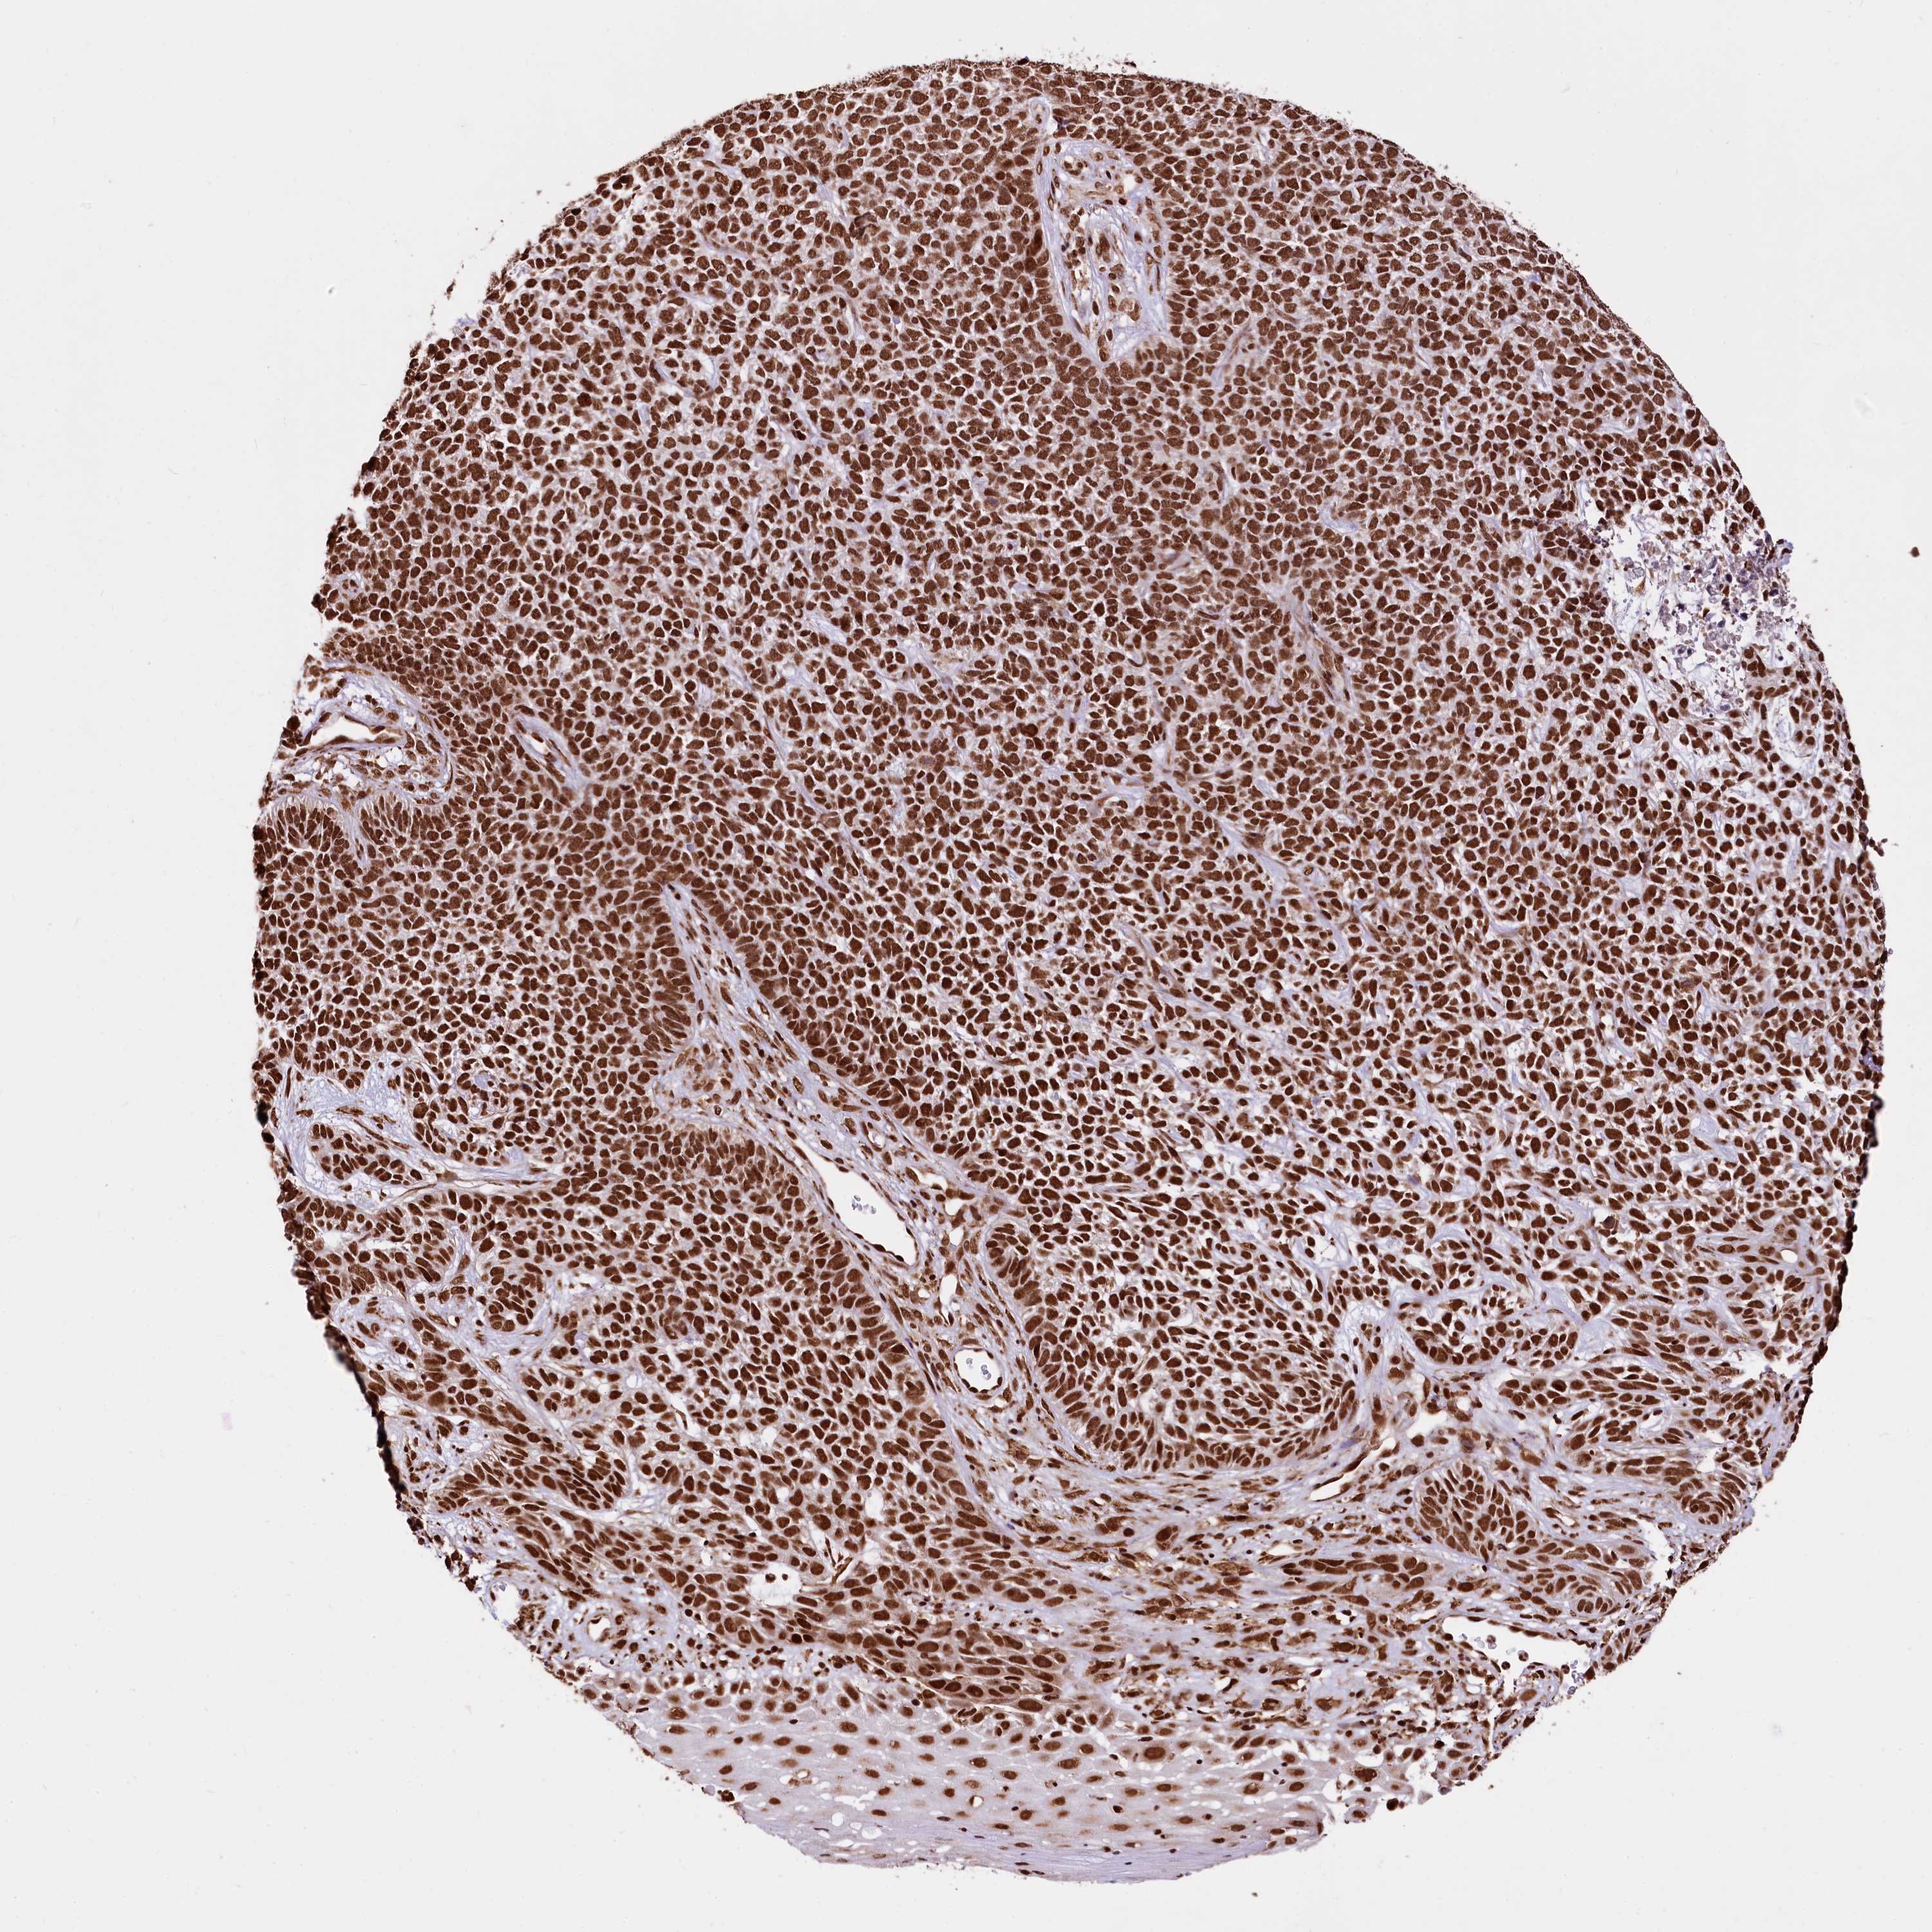

SKIN CANCER - Protein expressioni

A mouse-over function shows sample information and annotation data. Click on an image to view it in a full screen mode. Samples can be filtered based on level of antibody staining by selecting one or several of the following categories: high, medium, low and not detected. The assay and annotation is described here.

Antibody stainingi

Antibody staining in the annotated cell types in the current human tissue is reported as not detected, low, medium, or high, based on conventional immunohistochemistry profiling in selected tissues. This score is based on the combination of the staining intensity and fraction of stained cells.

Each image is clickable and will lead to virtual microscopy that enables deeper exploration of all samples and also displays staining intensity scores, fraction scores and subcellular localization as well as patient and tissue information for each sample.

Antibody HPA039513

Antibody HPA040015

Staining

High

Medium

Low

Not detected

Intensity

Strong

Moderate

Weak

Negative

Quantity

>75%

75%-25%

<25%

None

Location

Nuclear

Cytoplasmic/membranous

Cytoplasmic/membranous,nuclear

Basal cell carcinoma

Squamous cell carcinoma, NOS

Squamous cell carcinoma, metastatic, NOS